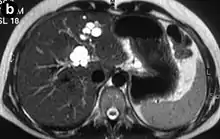

| Turbo spin echo T2-weighted axial MRI of Caroli disease, showing cystic dilatations of bile ducts (shown as white).[1] | |

Modern imaging techniques allow the diagnosis to be made more easily and without invasive imaging of the biliary tree.[9] Commonly, the disease is limited to the left lobe of the liver. Images taken by CT scan, X-ray, or MRI show enlarged intrahepatic (in the liver) bile ducts due to ectasia. Using an ultrasound, tubular dilation of the bile ducts can be seen. On a CT scan, Caroli disease can be observed by noting the many fluid-filled, tubular structures extending to the liver.[4] A high-contrast CT must be used to distinguish the difference between stones and widened ducts. Bowel gas and digestive habits make it difficult to obtain a clear sonogram, so a CT scan is a good substitution. When the intrahepatic bile duct wall has protrusions, it is clearly seen as central dots or a linear streak.[10] Caroli disease is commonly diagnosed after this “central dot sign” is detected on a CT scan or ultrasound.[10] However, cholangiography is the best, and final, approach to show the enlarged bile ducts as a result of Caroli disease.